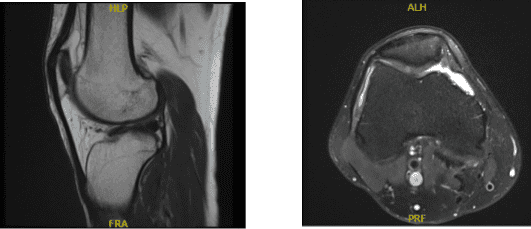

MRI Right Knee non-contrast

Degeneration of the medial meniscus with a horizontal tear involving its body. Tricompartmental degenerative changes, most pronounced in the medial femorotibial compartment. Moderate knee joint effusion.

The anterior cruciate, posterior cruciate, medial collateral, and lateral collateral ligaments are intact. There has been degeneration of the medial meniscus with a horizontal tear involving its body. No discrete lateral meniscal tears are present. The quadriceps and patellar tendons are intact.

The medial and lateral patellofemoral ligaments are unremarkable. A moderate knee joint effusion is present. Full thickness cartilage loss is present in the medial femorotibial compartment with associated subchondral bone marrow edema.

Less severe cartilage irregularity is present in the patellofemoral and lateral femorotibial compartments. Overall, the bone marrow signal is age-appropriate. There is no significant popliteal cyst. Popliteus muscle and tendon are intact. The iliotibial band is within normal limits. The posterior lateral corner is unremarkable.